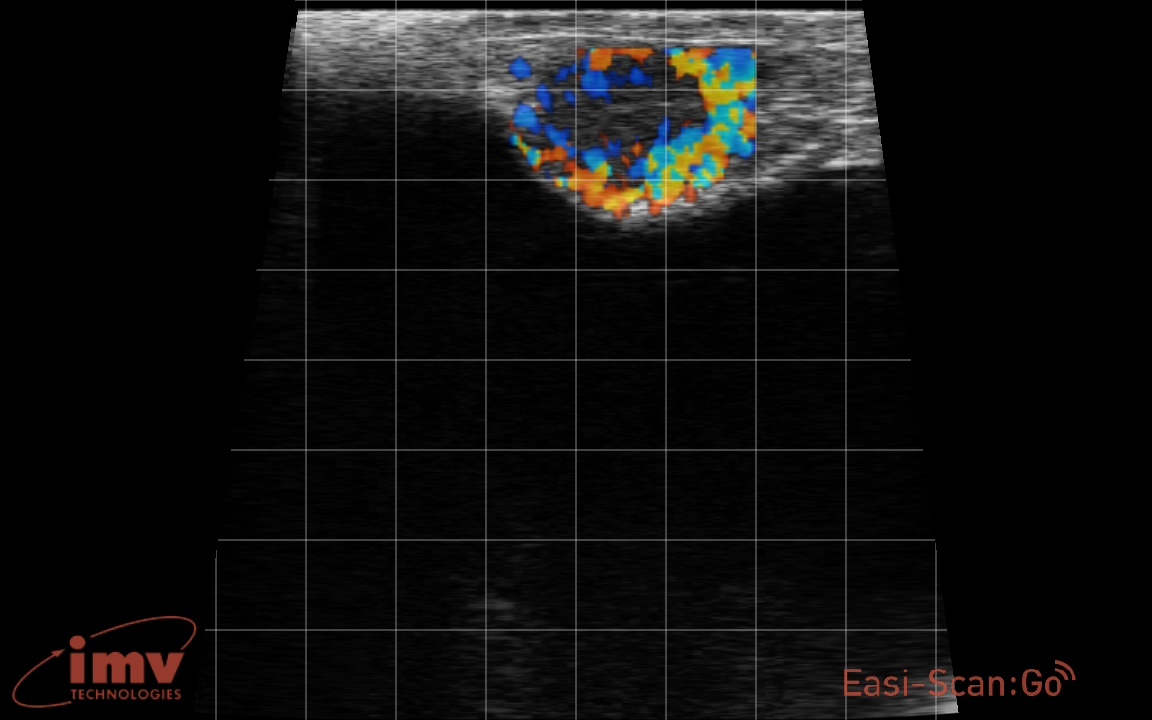

Яловая корова

Анализ научных публикаций показывает, что цветная допплерография демонстрирует 100% отсутствие ложноположительных результатов при оценке васкуляризации ткани яичника. Достоверность метода варьируется от 78% до 98,5% в зависимости от выборки и условий исследования.

Эти данные подчёркивают высокую надёжность цветной допплерографии для диагностики и мониторинга репродуктивных процессов у животных. Метод позволяет своевременно выявлять патологии, связанные с нарушением кровоснабжения яичников, что важно для повышения репродуктивной эффективности и продуктивности животноводства.